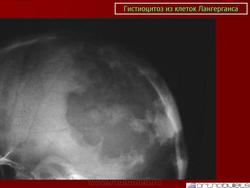

Гистиоцитоз из клеток Лангерганса